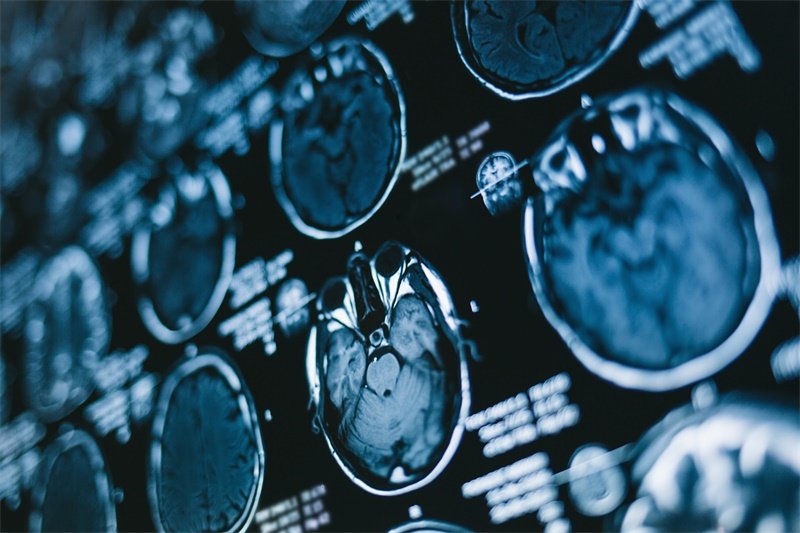

在MRI或CT影像上,如果医生发现了约 13mm 的占位性病变,患者自然会对该病变的性质产生疑问。这时,通常需要结合其他检查和临床症状,以判断其是否为恶性肿瘤、良性肿瘤、血肿等。具体的诊断过程包括 影像学检查、实验室化验 和临床表现等多个方面。

影像学检查是诊断的重要手段。CT或MRI可以提供详细的图像,帮助医生判断病变的性质和大小。影像学检查的结果将为后续的治疗方案提供依据。